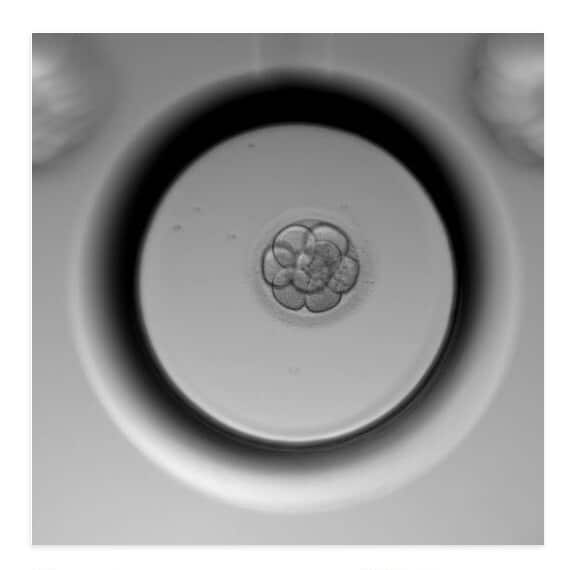

Amanda笑着说,等孩子长大,她会给他看自己还在培养皿里的照片,那是生命最原始最清晰的模样。